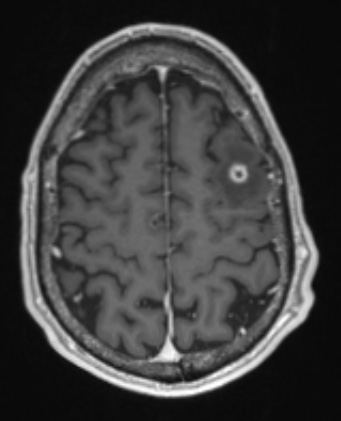

Washington University Experience | INFECTION | Bacteria | Abscess | Abscess, Early (Cerebritis - Initial Wall Formation) | 5A3 (Case 5) T1W - Copy

This T1-weighted scan with contrast shows a rim enhancing nodule with marked surrounding edema.